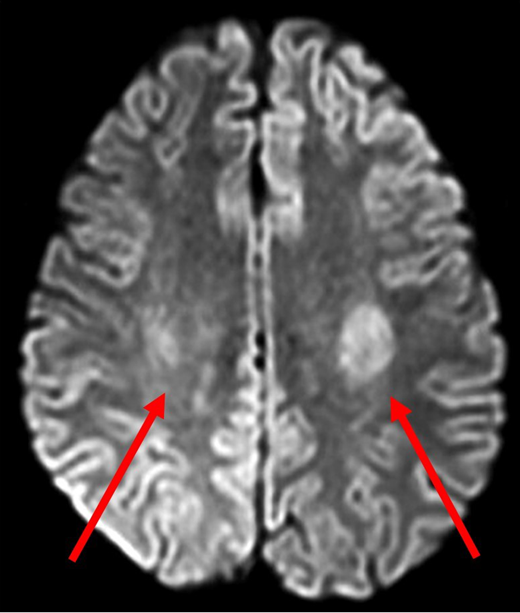

A 14-year-old Hispanic girl with high-risk B-ALL without CNS involvement was receiving standard-of-care chemotherapy according to the Children's Oncology Group protocol AALL0232. She had tolerated chemotherapy relatively well, including 6 doses of intrathecal methotrexate in the induction and consolidation phases. The first interim maintenance phase was initiated with 15 mg of intrathecal methotrexate followed by 5 g/m2 of intravenous methotrexate over 24 hours. Methotrexate cleared appropriately, and she received 3 doses of leucovorin 15 mg/m2 at hours 42, 48, and 54. Nine days later, she presented to the emergency department with acute-onset right-sided leg weakness, which progressed to the right arm and face over a 2-hour period. In addition to right paraparesis and facial droop, she was noted to have aphasia and dysarthria. Magnetic resonance imaging (MRI) performed 4 hours after the onset of symptoms showed restricted diffusion bilaterally in the centrum semiovale, greater on the left side (Figure 1). She was admitted to the intensive care unit for close observation. During the next 24 hours, her speech worsened, and she became more confused. There was moderate improvement in right-sided weakness, but she developed weakness in the left arm and leg. With continued supportive care, beginning day 3 of hospitalization, her symptoms gradually improved, facial asymmetry resolved, her speech became clearer, and she was able to swallow. She required physical therapy for 2 more days to regain her baseline strength and ambulate independently.

Diffusion-weighted MRI of patient 1 four hours after onset of symptoms. DWI demonstrated abnormal diffusion in bilateral centrum semiovale (red arrows), greater on the left side. These findings indicate increased diffusion of water in the affected regions suggestive of cytotoxic edema.

Leukoencephalopathy or subcortical white matter changes are the characteristic MRI findings of methotrexate neurotoxicity. Diffusion-weighted imaging (DWI) is the most sensitive modality during the acute phase and shows abnormally high diffusion of water in brain areas that correspond with clinically apparent neurologic deficits.12 Because changes noted on DWI can be transient, a negative MRI does not exclude a diagnosis of methotrexate neurotoxicity. On the other hand, white matter hyperintensities in T2-weighted and fluid-attenuated inversion recovery MRIs can persist and evolve over time; therefore, awaiting complete normalization of MRI findings prior to rechallenge with methotrexate is not practical.